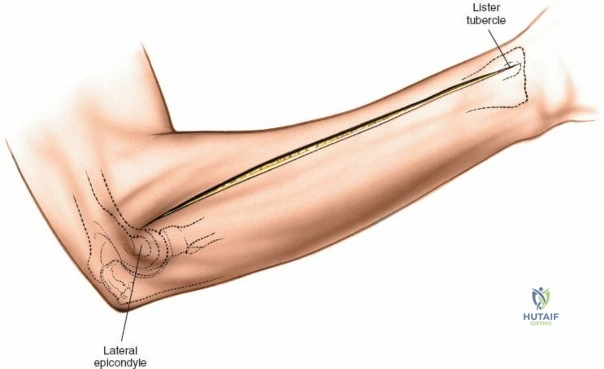

Accurate identification of surface landmarks is the first step in a successful Henry approach. Palpate the biceps tendon, a stout, taut structure crossing the anterior elbow joint just medial to the brachioradialis muscle. Next, palpate the brachioradialis itself, the fleshy muscle forming the lateral border of the cubital fossa. Finally, identify the styloid process of the radius distally. Note that when the forearm is fully supinated (the anatomic position), the radial styloid is truly lateral.

Make a straight or gently curved incision beginning at the anterior flexor crease of the elbow, just lateral to the biceps tendon. Extend this incision distally toward the styloid process of the radius. The exact length and placement of the incision are dictated by the specific pathology; the approach is highly modular, and often only the proximal, middle, or distal third of the incision is required.